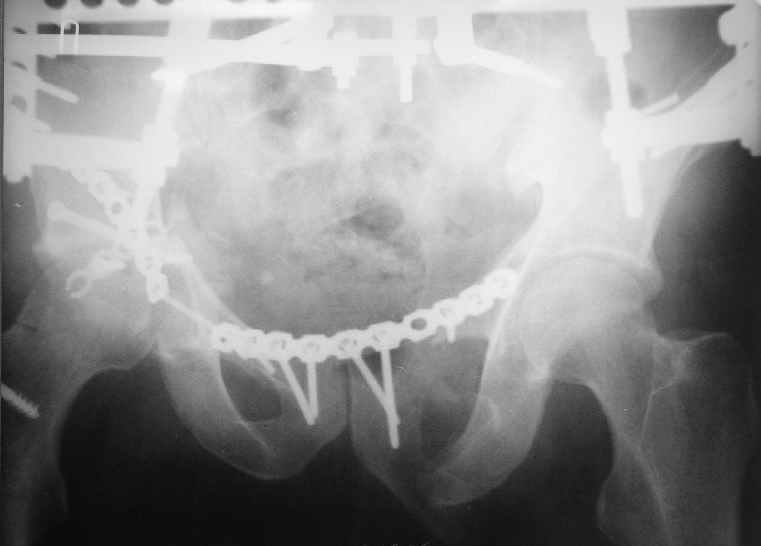

Уважаемый Антон, у Вашего больного имеется транстектальный поперечный перелом вертлужной впадины с переломом заднего края, перелом заднего типа, подвздошный вывих, возможна импрессия и повреждение нерва. Головка при этих повреждениях в нагружаемой части должна быть целой.

Фиксация передней колонны трансфрактурным винтом, задней пластинами,мостовидной и упорной.

Высылаю нечто подобное, аппарат пусть не смущает, просто больного оперировал через 2 месяца после травмы, а у него еще полный разрыв кп сочленения с контрлатеральной стороны.